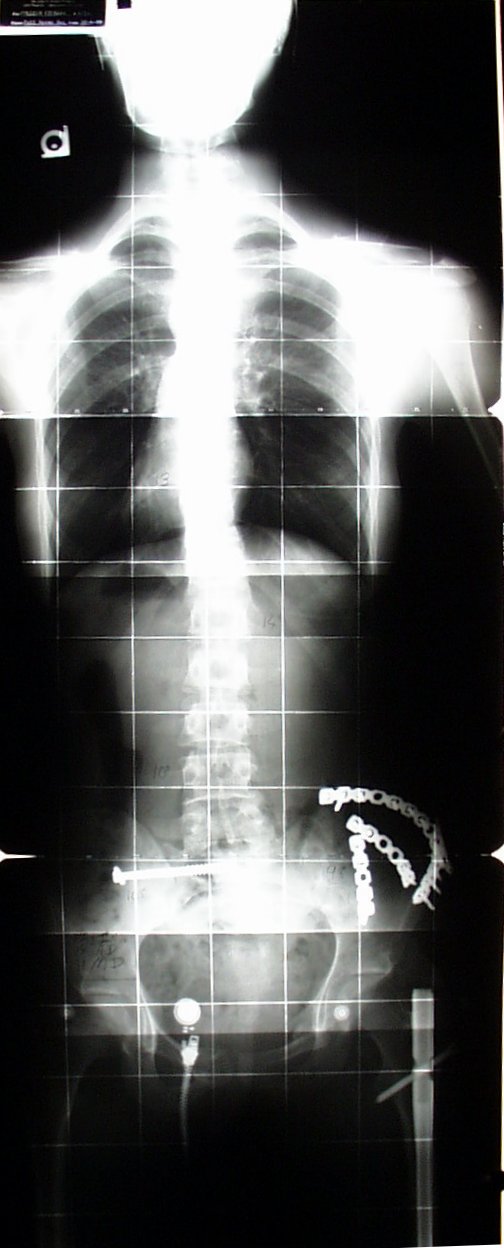

This X-ray was taken nearly 2 years after a MAJOR auto accident.

You can see part of the rod I had taken out.

I still had it at this point.